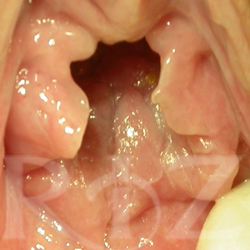

• 치료 전 사진

치료 후 사진

나이 : 26 / 출산경력 : 0 / 이름 : 정OO

레이저처녀막수술  LMH™(Laser Micro Hymenoplasty™)

- Before :  처녀막 부분이 손상되어 질 입구가 벌어진 상태

- After : LMH 수술 후 손상된 부분이 거의 완벽하게  복구 됨